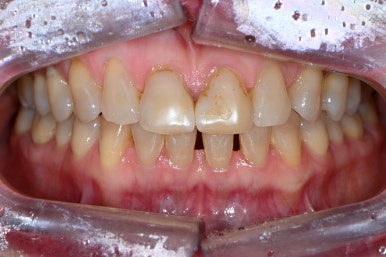

앞니 레진치료를 오랫동안 받아왔는데, 변색 때문에 괴로워요..

앞니 벌어짐도 해결하고 싶어요.

앞니 벌어짐과 앞니 레진 변색을 해결하고 싶은 마음에 압구정 치과에 방문하신 환자분입니다.

잘 보시면, 떼워놓은 앞니 레진 경계가 변색이 되서 갈색으로 보이시는 걸 확인하실 수 있죠??

파란색 빗금친 부위가 대략적으로 레진이 붙어있는 부위입니다.

물론 이만큼 레진으로 치료해내는 것부터 정말 고수이셨을 겁니다.

그렇지만, 시간이 지남에 따라 생기는 레진 변색은 거의 필연적이죠... 결국은 재치료 또 재치료....

빨간색으로 표시된 부위는 가운데 앞니의 빈틈을 메우기 위해 레진을 치아 옆에 붙여놓은 곳입니다.

그래도 요기는 변색은 없네요! 다만 색상의 부조화가 조금 있네요 ^^;;

위 치아만 보면 변색이 더욱 도드라집니다. 치아가 얼룩덜룩하죠.?

계속 레진치료만 할 수도 없는 노릇입니다. 변색이 또 생기면 기존 레진 제거하고 더 넓게 떼우고... 또 레진 변색 생기면 더 넓게 떼우고...

씹는 면에서 보시면 더욱 문제점이 잘 보입니다.

앞니 사이에 공간도 많으시고... 기존의 레진은 하염없이 두껍게만 붙여나가고 있는 수순이고..

앞니 벌어짐 + 레진 변색은 정말로 라미네이트 치료를 받기에 가장 적합한 경우라고 생각합니다.